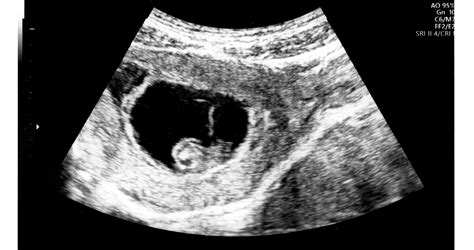

A diagnosztika az elmúlt évtizedekben jelentősen fejlődött. Míg korábban a méhnyak-terhességet gyakran csak műtét során ismerték fel, ma a korai terhességi ultrahangvizsgálat kulcsszerepet játszik a felismerésben. A transzvaginális ultrahang lehetővé teszi, hogy az orvos pontosan lássa a petezsák elhelyezkedését. Cervikális graviditás esetén a terhességi zsák a méhnyakcsatornában helyezkedik el, a méh ürege üres, a belső méhszáj zárt, és jellegzetes „homokóra” alak figyelhető meg. A korszerű Doppler-ultrahang vizsgálat kimutathatja a trophoblast fokozott keringését is, ami segít elkülöníteni az állapotot egy vetélés során a méhnyakba csúszó terhességi szövettől.